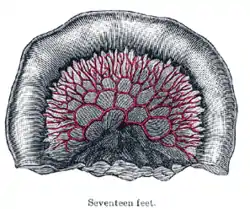

Toward the ileocolic junction, secondary and tertiary loops are observed, the vessels are smaller and become obscured by numerous fat-tabs.

The diagrams below show the arrangement and variations of the loops of the mesenteric vessels for various segments of the small intestine of average length: